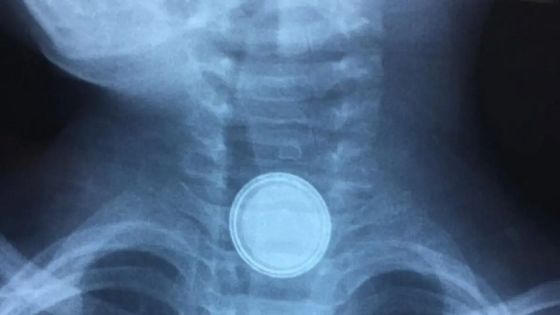

وطنا اليوم:قال أحد المواطنين إن ابنه، البالغ من العمر عامين ونصف، تعرّض لمضاعفات صحية خطيرة بعد ابتلاعه بطارية استقرت في المريء، حيث جرى التدخل الطبي لإخراجها، إلا أن حالة الطفل تدهورت لاحقًا وبدأ يستفرغ دمًا، قبل أن يتبيّن وجود ثقب في المريء وتأثر شريان رئيسي في القلب.

من جانبه، أوضح المدير الطبي في مستشفيات البشير الدكتور مؤيد القضاة، أن ابتلاع البطاريات يشكّل خطرًا بالغًا على حياة الأطفال، مبينًا أن البطارية تحتوي على مادة قلوية حارقة وسامة، وفي حال تحللها داخل الجسم قد تؤدي إلى ثقوب في الجهاز الهضمي ونزيف داخلي قد يهدد الحياة.

وأشار القضاة إلى أن ما رواه والد الطفل يندرج ضمن تسلسل المضاعفات المعروفة لابتلاع البطاريات، لافتًا إلى أن المادة القاعدية تحللت داخل الجسم وتسببت بحدوث ثقب في المريء، ما أدى إلى تضرر الشريان الأبهر المجاور، وهو الشريان الرئيسي المسؤول عن ضخ الدم إلى الجسم، إضافة إلى احتمالية تأثر العصب الأبهر.

وبيّن أن الطفل خضع لعملية جراحية نوعية استمرت نحو 8 ساعات، تم خلالها علاج الثقب وإجراء رقع للشريان الأبهر.